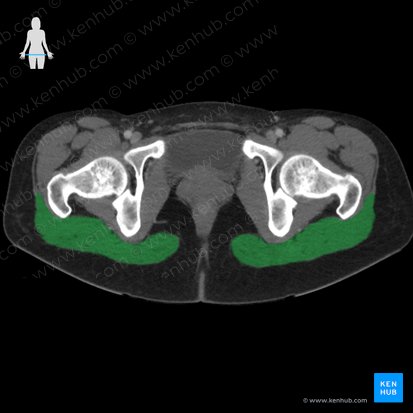

The gluteus maximus muscle is the largest of three gluteal muscles (other two are gluteus medius muscle and gluteus minimus muscle). By laying over the gluteus medius and minius muscles, it builds the most superficial layer of the dorsal gluteal musculature and thus forms the surface anatomy of the gluteal region.

The muscle originates from the sacrum (posterior part), ilium (behind the posterior gluteal line), the thoracolumbar fascia and the sacrotuberous ligament.

Its inferiormost fibers insert at the gluteal tuberosity of the femur. On the contrary, the more superior fibers go over into the iliotibial tract, a strong fibrous band at the outside of the thigh inserting at the lateral condyle at the tibia. The gluteal fold (or crease) does not represent the lower margin of the muscle but rather results from an arcuate enhancement of the fascia.